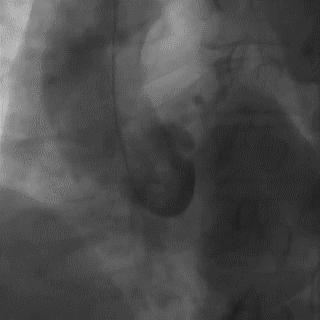

操作:升主动脉造影,寻找静脉桥血管

➢ CASE 3

AL1.0

➢ CASE 4

➢ CASE 5

升主动脉造影未见桥血管显影,原位血管造影也没发现竞争血流迹象,可以确定桥血管已闭塞,必要时可以借助冠脉CTA辅助诊断